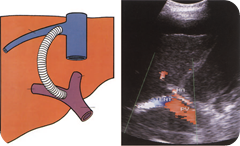

TIPS is a percutaneous method used to relieve the symptoms of portal hypertension in cirrhotic patients. It connects the portal vein directly to the right hepatic vein with an expandable metal shunt A catheter and guide wire are passed, under X-ray control, through the jugular vein to the inferior vena cava (IVC) and into the hepatic vein. A pathway is then forged with a needle through the liver parenchyma to join the PV with the insertion of a shunt to keep the channel open. Portal venous blood then effectively bypasses the liver, flowing straight into the hepatic vein. This usually results in the speedy decompression of varices and improvement of other symptoms of portal hypertension.

Ultrasound may be used to monitor stent patency (Fig. below). Shunt stenosis or occlusion is a common problem, particularly in long-term shunts; this can be detected with routine postprocedure ultrasound screening and treated with reintervention. The most common site for a stenosis is at the junction of the stent with the PV. The velocity of blood flow in the shunt should be between 1 and 2 m/s and this should be consistent throughout the stent. A variety of Doppler parameters can be used to detect the malfunction of the shunt. A shunt velocity of less than 50 cm/s is a sign of stenosis but this has not been reproducible in all institutions, and other factors such as a change of 50 cm/s or more from the baseline scan, a localized elevation of velocity at the stenotic site (with an upper limit of normal of up to 220 cm/s) or an increase in the velocity gradient (as the stenotic stent exhibits an increased maximum velocity and a decreased minimum velocity) are also poor prognostic signs. TIPS is regarded as a temporary measure but can considerably improve the patient’s condition pending treatment of chronic liver disease, relieving haemorrhage from varices, relieving intractable ascites and stabilizing liver function. It is increasingly used as a bridge to liver transplant. It is also used as an alternative to surgery in patients who are poor surgical risks, although the diversion of blood away from the liver can result in adversely affected liver function and eventual encephalopathy.

Ultrasound images of Transjugular intrahepatic portosystemic shunt (TIPS) & TIPS shunt in a patient with severe portal

hypertension. The higher-velocity MHA is seen anterior to the shunt, which demonstrates flow from right to left of the

image.